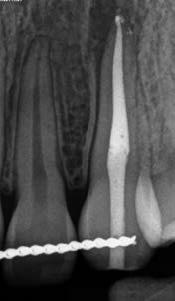

Egy 38 éves nőbeteg a korábban kezelt jobb felső második kisőrlőfogából (1.5) kiinduló mérsékelt fájdalom miatt jelentkezett rendelésünkön. A kórtörténetében jelen panasza szempontjából releváns információ nem szerepelt. A beteg a klinikai vizsgálat során vertikális kopogtatásra enyhe érzékenységet jelzett. A kérdéses fog körül mérhető szondázási mélység és a fogmobilitás fiziológiás volt. Periapicalis röntgenfelvételen egy, a fog gyökércsúcsán túl presszálódott betört gyökérkezelő műszerből származó eszközfragmentumot láttunk (2. a. ábra). A preoperatív CBCT-felvétel a buccalis csontlemez épségét igazolta (2. b-c. ábra). A fog revíziója öt hónappal korábban történt. A már előzőleg gyökérkezelt, gyökértömött, majd revideált 1.5-ös fog esetében a diagnózisunk periodontitis periapicalis symptomatica volt. A periapikális elváltozás kezelése érdekében navigált endodonciai mikrosebészeti beavatkozást végeztünk.

A felső állcsontról intraorális szkent (TRIOS) készítettünk, és az ezáltal kapott STL fájlt (2. d. ábra) a CBCT-felvétel során nyert DICOM fájlokkal a Zirkonzahn.Implant-Planner (Zirkonzahn) szoftverben egyesítettük. A sebészi sablont ebben a programban megterveztük, majd a Meshmixer (Autodesk) szoftver se-

gítségével tovább módosítottuk. Az így kapott sebészi sablon egyértelműen meghatározta a periapikális terület eléréséhez szükséges csontablak határait (2. e-f. ábra) Helyi érzéstelenítést követően teljes vastagságú mucoperiostealis lebenyt képeztünk, majd a buccalis csont feltárását követően (2. g. ábra) a sablon segítségével bejelöltük a preparálandó csontablak határait (2. h. ábra). A csontablak kialakítása során Piezotome CUBE LED kézi-darabot alkalmaztunk, majd a leemelését követően a betört eszközt megkerestük (2. i. ábra) és eltávolítottuk (2. j. ábra). A rezekciót ultrahangos megmunkáló fejekkel (ACTEON) végeztük, majd retrográd preparáció következett.

A retrográd gyökértömés elkészítése során TotalFill BC RRM Fast Set Putty-t (FKG) használtunk (2. k. ábra). A lebeny széleit 5/0-s Prolene varratokkal egyesítettük (2. l. ábra). A varratok a műtétet követően 72 órával kerültek eltávolításra. A beteg két évvel később kontrollröntgen készítése céljából érkezett rendelőnkbe. A vizsgálat során a fog tünetmentesnek és funkcióképesnek bizonyult (2. m. ábra).

a-m. ábrák: Preoperatív röntgenfelvétel (a) és preoperatív CBCT-felvétel a jobb felső 5-ös (1.5) fogról, sagittalis (b) és axialis (c) nézetek. Az intraorális szkennelés során kapott STL-fájl (d). A 1.5-ös fog navigált endodonciai mikrosebészeti beavatkozásához tervezett sablon (e). A 1.5-ös fog navigált endodonciai mikrosebészeti beavatkozásához nyomtatott sablon (f). Teljes vastagságú mucoperiostealis lebenyt emeltünk (g). A sablont a helyére illesztettük, és a csontablak határait jelöltük (h). A fog gyökerén kívül eső, betört eszköz a 1.5-ös fog periapicalis régiójában (i). Az eltávolított betört eszköz (j). A rezekció, retrográd preparáció és a TotalFill BC RRM Fast Set Putty anyaggal elkészített retrográd gyökértömés utáni röntgenfelvétel (k). A lebenyt varratokkal rögzítettük (l). A kétéves kontroll során készített röntgenfelvétel (m).